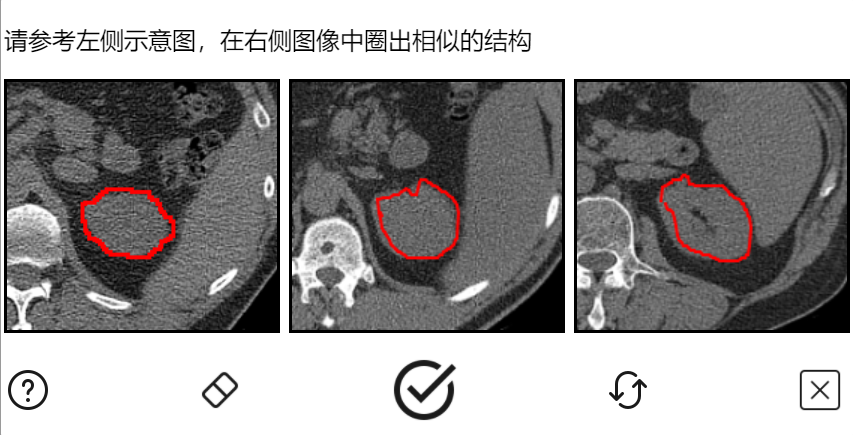

今年年初,我记得腾讯和深圳大学一起搞了个医学验证码,用来验证的是医学影像图片,背后的目的是提高 AI 标注和诊断的成功率。

不得不说,相比谷歌来说,小企鹅的这个项目更有爱一些。

而且这还是一项公益项目,虽然验证起来可能会更麻烦了些,但我相信碰到这个验证码的人,会停下多花这么几秒,让这个验证码更精准些。